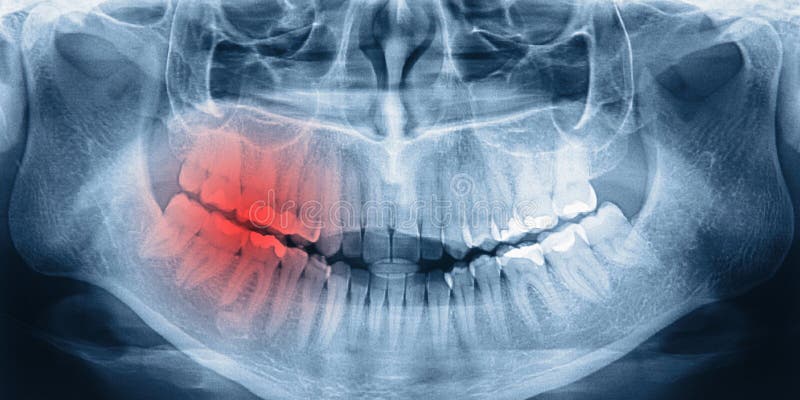

WebHay varios aspectos en los que fijarse: Color. Los dientes de leche son más blancos que los permanentes. Bordes. Los dientes de leche son suaves en la parte de abajo, mientras. WebAunque esta patología puede darse en los dientes de leche, suele ser más frecuente que suceda en los dientes permanentes o definitivos, siendo común en los. WebLa odontopediatría es el área de la odontología especializada en cuidar los dientes de los niños, tanto los temporales como los definitivos.. Al contrario de lo que. WebEn su boca estaban los 16 dientes de leche, ya había perdido los incisivos temporales inferiores, 10 arriba y 6 abajo. Y creciendo en sus encías para sustituirlos. WebEs sencillo, llama a Aguilar Dental Salut (934 151 113) y pide hora con la Odontopediatra. Te dará un diagnóstico después de hacerle una ortopantomografía para. WebEl Equipo Novasmile. 4 julio 2012. 599. Muchos adultos aún conservan los dientes de leche y se preguntan si los definitivos les saldrán alguna vez, si carecen de. WebEn esta nueva edición de #SabíasQué..., Jacobo nos explica algo que suele dar mucha curiosidad a los padres primerizos: la aparición de los dientes definitiv... WebLos dientes de leche tienen una capa de esmalte dental y es muy delgada, puesto que el trabajo de estos será menor. Además de que la permanencia de los. WebNormalmente a los 5 o 6 años empezamos a sustituir los dientes provisonales por los definitivos, sin embargo hay adultos que continúan durante años. WebRadiografia de los dientes de leche junio 27, 2022 admin . Radiografía de los dientes de un niño de 5 años “Dentro de cien años no importará cuál era mi cuenta.